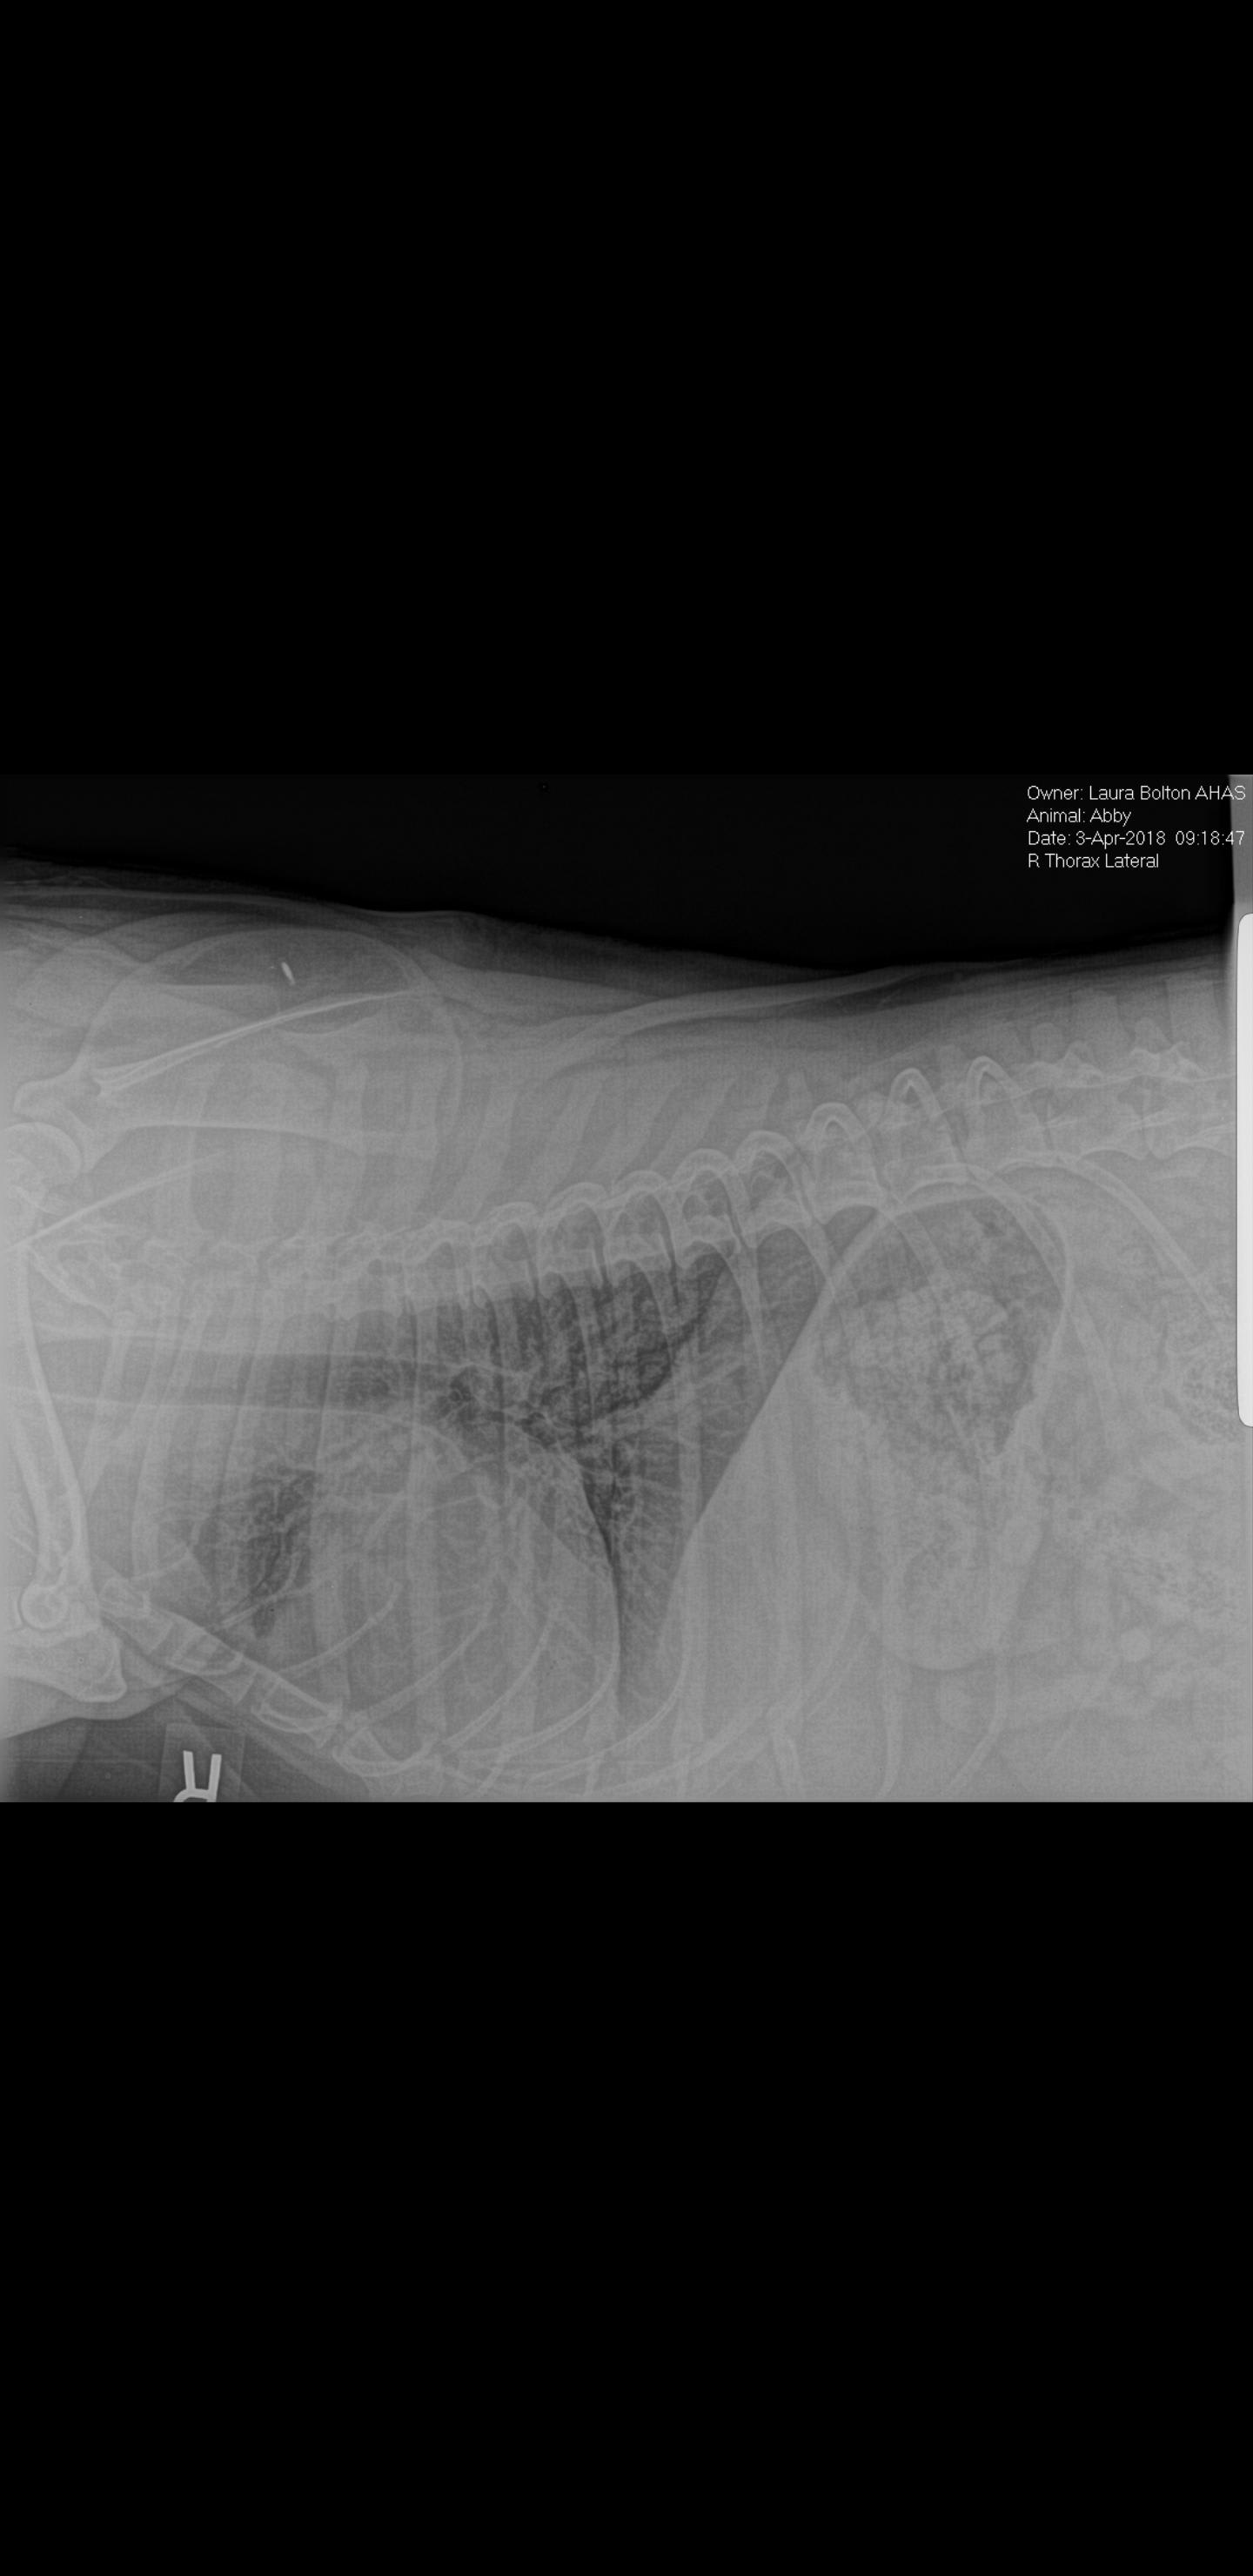

My dog was diagnosed with Squamous cell carcinoma and we had the toe amputated. Our vet is confusing us on her survival rate and we just want a second opinion. Please be bold and upfront with us. How long does she have? If it didn't metastasize to her lungs I know she has a bit longer we will do xray every 6 months now to be sure. Do u think she has a year? Two? Could she live out a normal long life if it's all gone? I've attached pics. Thanks

survival rates are just statistics. If you have a 95% survival rate for x amount of years, there will still be 5% of those who will not survive that time. At the end of the day is is either you live long or you don't. That said, the pathology report is actually very favorable 1) the surgeon managed to remove the tumor in its entirety with good margins (well into the healthy tissue) 2) The cells of the tumor are well differentiated: this means it was slow growing and usually does not metastasise 3) considering your dog is already 6 years old,, and a large breed, the natural life expectancy is maybe another 6 to 8 years maximum. The fact that the tumor was removed in its entirety with good margins, no lymph nodes were involved and no lung metastases present means that it is likely not going to recur. If you regularly check your dog's paws and skin and have any suspicious findings examined right away, you can catch any recurrences early and they can be dealt with. Overall I would not worry too much about survival rate. I think Abby has a good chance for a long happy and healthy life. Nothing is certain with a living being, but the chances are good!